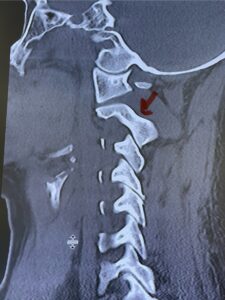

Fig. 6b: Sagittal cervical CT scan demonstrating normal thickness of the left C2 isthmus (red arrow)